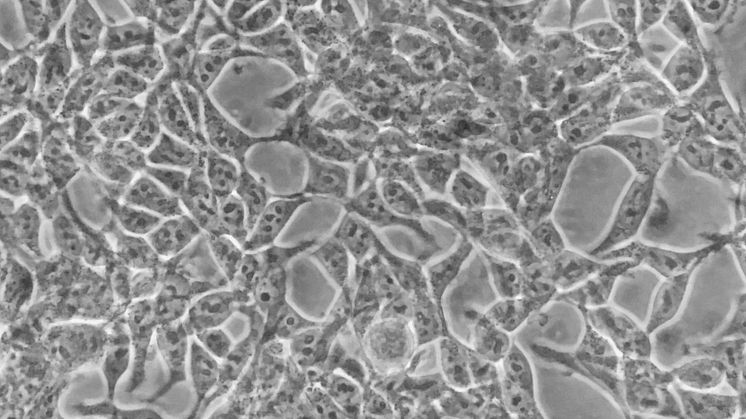

• Human kidney cells

In the present study, old standard inverted microscopes that are very abundant at Universities and hospitals were upgraded to high quality live imaging stations using a few 3D-printed parts, off-the-shelf electronics, and a smartphone. It was shown that the resultant upgraded systems provided excellent cell culture conditions and enabled high-resolution imaging of living cells.